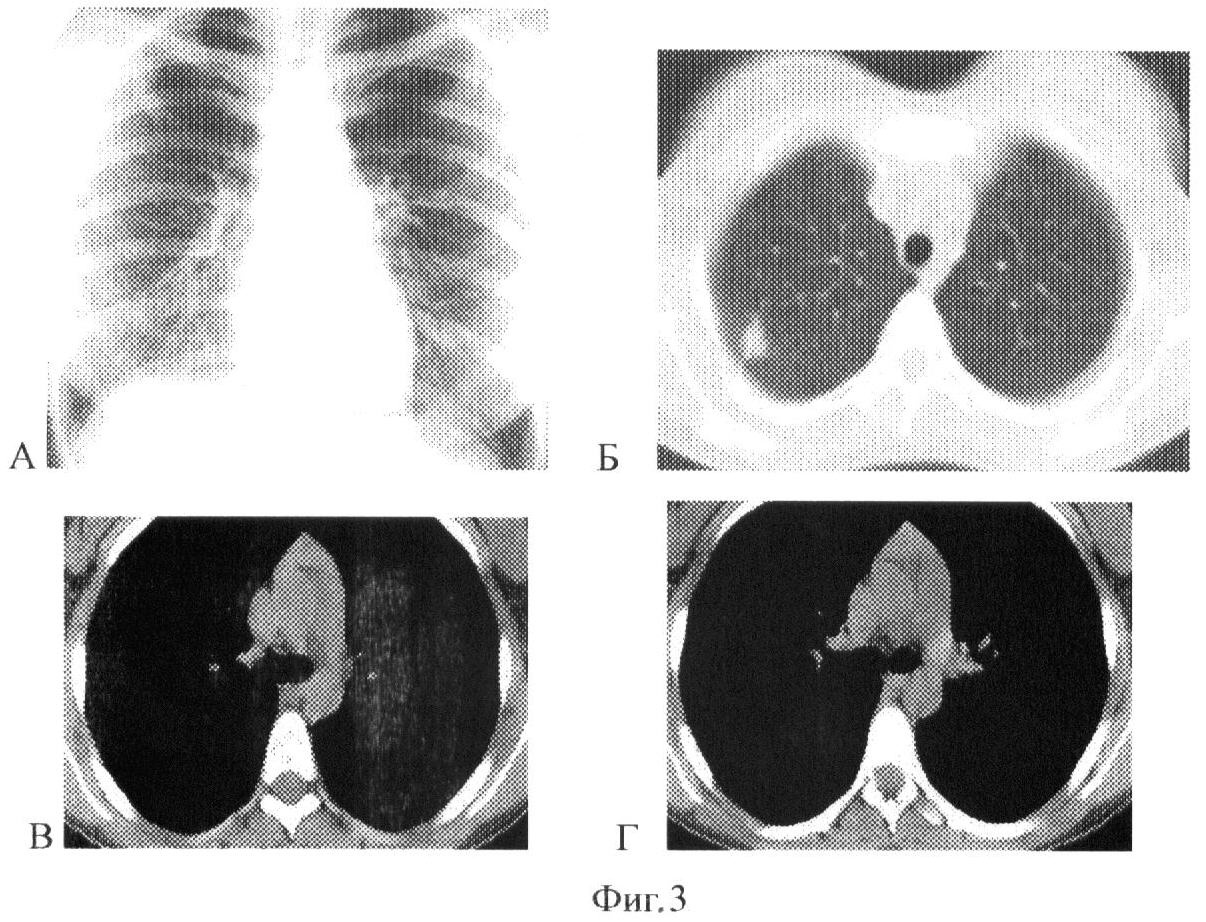

Сущность предлагаемого изобретения представлена на фиг.1, 2 и 3. На фиг.1 – данные рентгенологического обследования больного (пример 1), на фиг.2 и 3 – данные рентгенологического обследования больного (пример 2).

При контрольном СКТ обследовании через 2,5 месяца (Фиг.3-А, Б, В, Г) отмечается закрытие полости деструкции с трансформацией его в казеозно-некротический фокус размером 1, 2 см, с рассасыванием значительной части очагов вокруг. Регрессия размеров лимфатических узлов нижней правой паратрахеальной и бифуркационной группы до 0,6 см. На основании отсутствия тенденции к слиянию в конгломераты и изменения структуры лимфатических узлов сделан вывод о реактивном характере гиперплазии, что подтверждается быстрой регрессия со стороны лимфатических узлов.